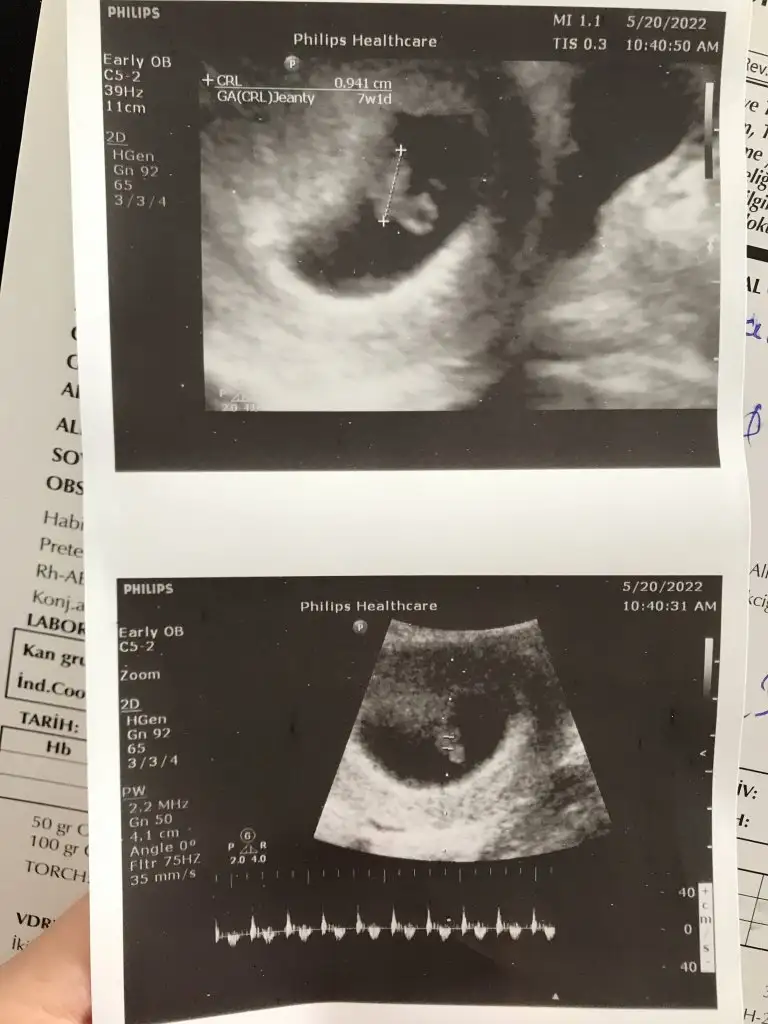

paşacık geliyorCinsiyet tahmin eder misiniz bu konuda tecrübeli bilen arkadaşlar yardımınızı rica ediyorım 10+6 yız bu resimlerde

Tahmin dogru cikti doktorum 13. Haftada erkek dedi. Tesekkur ederimmmpaşa gibi

birinde bebek henüz yok diğerinde ise yolk sac çok büyük tahmin yapılamazmerhabalar 7 haftalık vajınadan ikiz bebek

paşa gibi7+1 karından usg canım